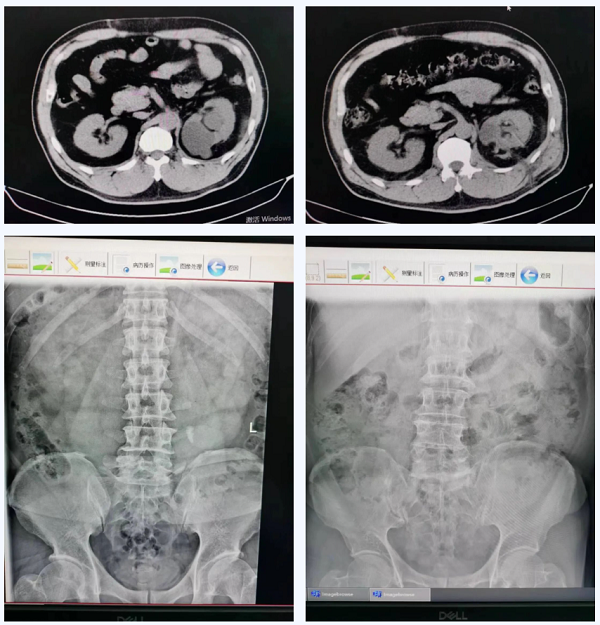

经过泌尿外科团队的精心准备,采用B超引导下,先行经皮肾钬激光肾结石碎石取石术,再在肾镜下用钬激光切开囊肿行肾囊肿去顶术治疗。术后,袁大哥已痊愈出院,其对手术效果非常满意。

术前术后对比图